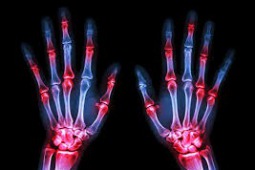

Zastosowanie tofacytynibu w leczeniu chorych na reumatoidalne zapalenie stawów - stanowisko ekspertów PTR

Reumatoidalne zapalenie stawów